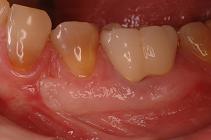

(その3) 奥歯がむし歯で使えなくなってしまった。

20代の女性。

治療した右下の奥歯が痛み、

他院で何度も根の治療を受けましたが

完治しないため、当院にお見えになりました。

なんとか残そうと試みましたが、

どうしても痛みが引かないため、

患者さんの了承を得て、抜歯となりました。

問題の歯を抜くと同時に、奥の親知らずを

問題の歯があった部分に移植しました。

術後約6ヶ月後の治療結果です。

抜いたところの骨の状態もきれいに治って、

しっかり噛める状態に回復できました。

患者さんも満足されて、たいへんよかったです。